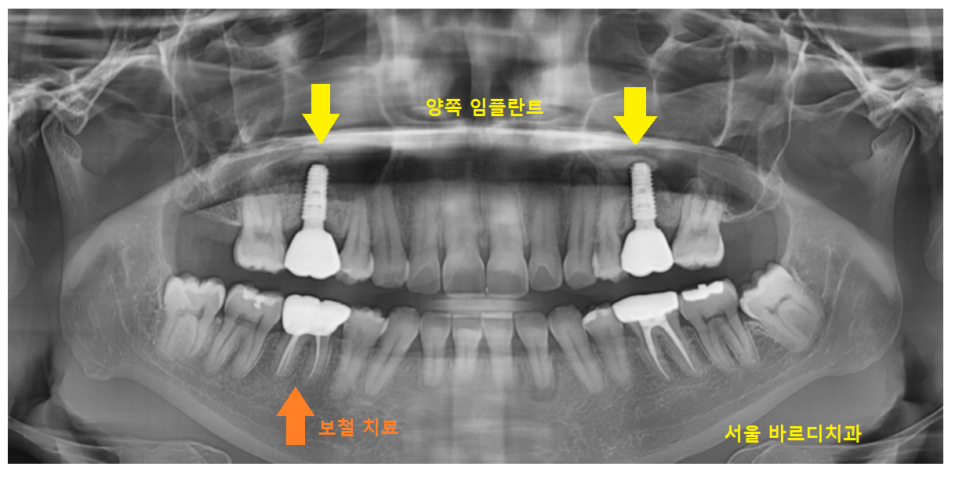

24.07.12

4개월정도 지나 치료가 완료되었습니다.

양쪽으로 치료를 동시에 시행했을 때의 장점

치료도 똑같이 끝납니다!!